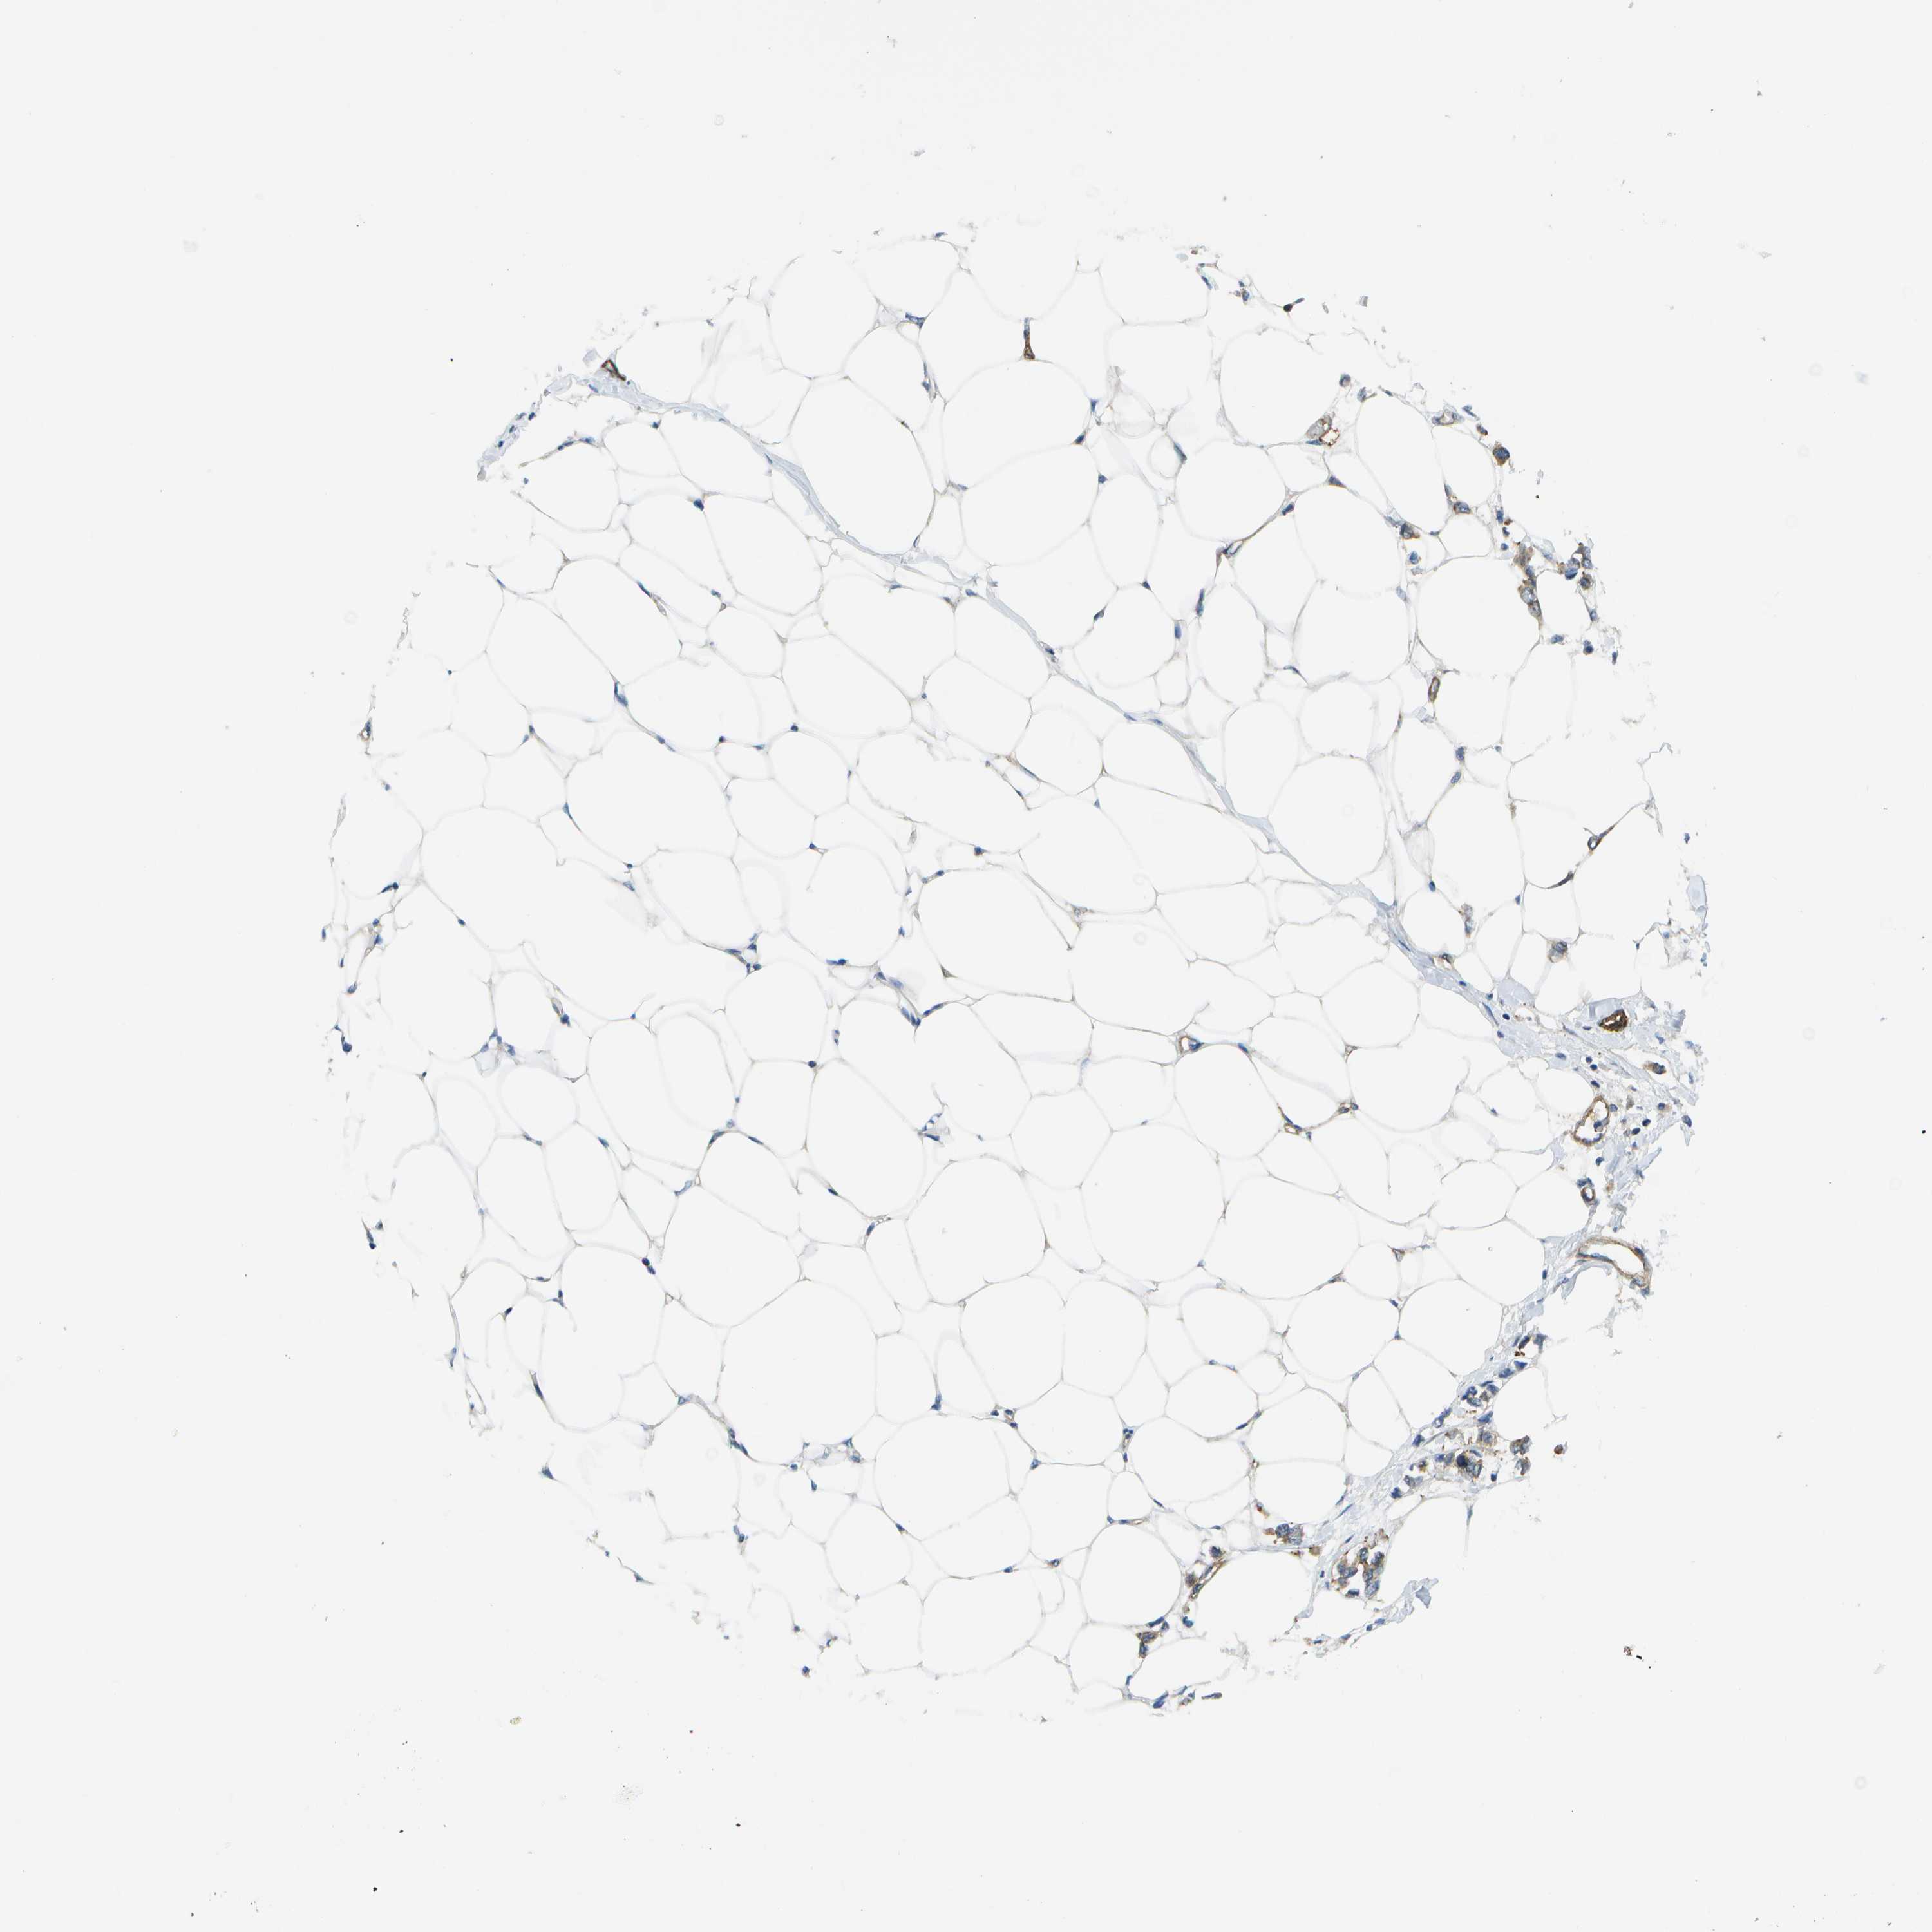

BRCA TCGA BRCA VALIDATION PROTEIN EXPRESSION

ANTIBODIES

AND

VALIDATION